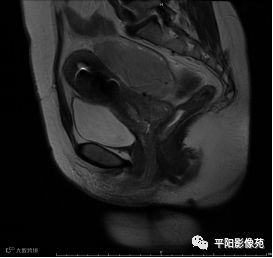

MRI表现

T2矢状位

(宫腔内见金属节育环伪影)宫颈区见不规则形等T1稍长T2信号软组织肿块,DWI序列呈明显高信号,大小约为3.87cmX2.64cm,双侧宫颈基质低信号环连续性中断,病灶向子宫右后上方生长,周围脂肪间隙模糊,增强扫描明显强化,强化程度低于子宫及宫颈实质;子宫后方、子宫直肠间隙见不规则形长T1长T2信号软组织肿块,DWI序列呈高信号,大小约10.12cmX4.82cmX10.29cm,病灶呈分叶状,向下方生长与宫颈分界不清,与直肠分界尚清,增强扫描明显不均匀强化。